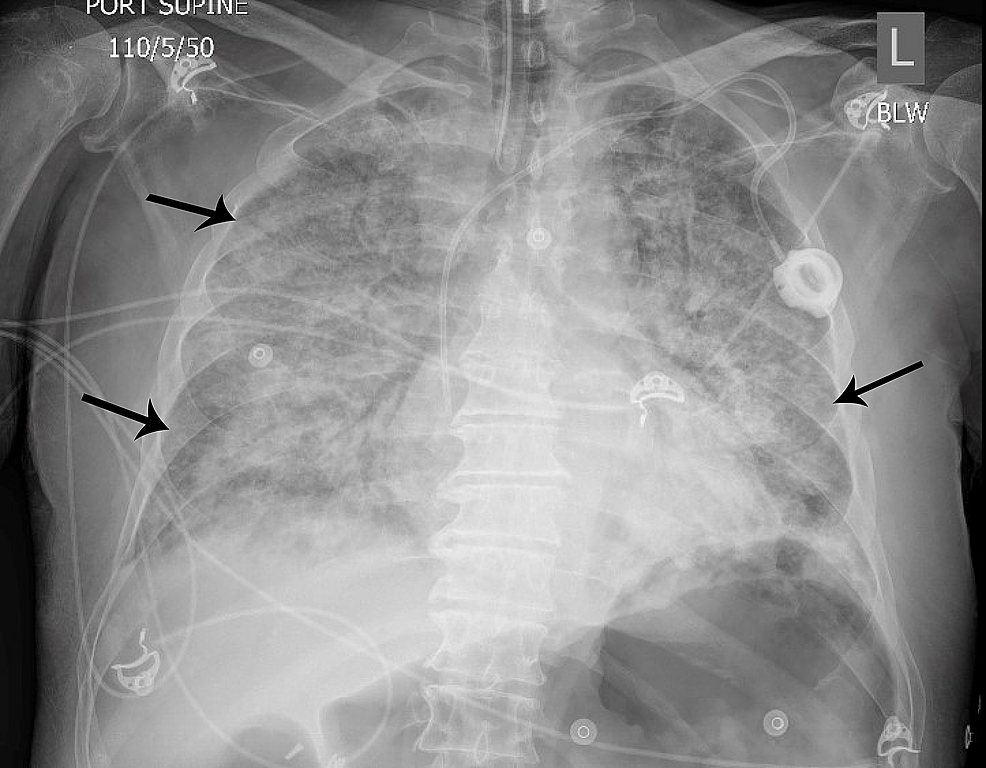

From www.cureus.com

Rhabdomyolysis in a Patient With Coronavirus Disease 2019 Cureus What Is An Lung Infiltrate Lung infiltrates can show up during screening tests and may be a. Diagnosis of pulmonary disease is typically based upon consideration of presenting symptoms, physical examination, and pulmonary function testing in combination with classification of. Persistent pulmonary infiltrate results when a substance denser than air (e.g., pus, edema, blood, surfactant, protein, or cells). Unusual substances in your lungs are known. What Is An Lung Infiltrate.